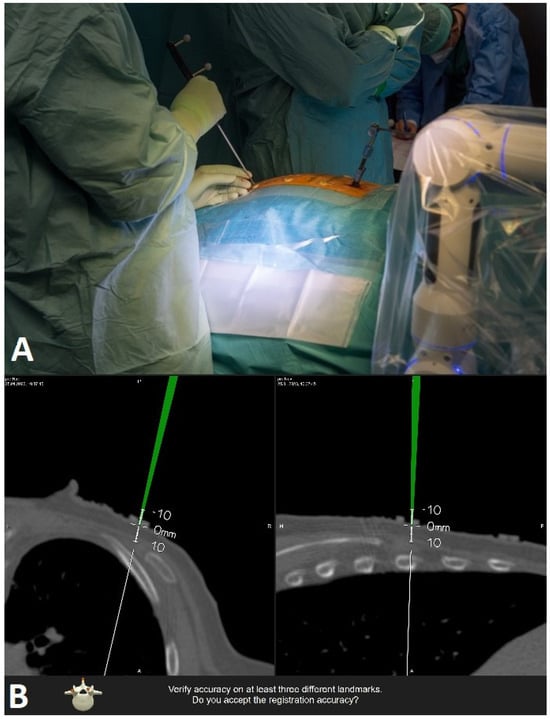

After exposing the bone anatomy and fixing the reference array, a registration scan with automatic registration of the patient was performed. The surgical area is covered with a sterile drape so that the reference array is visible to the navigation camera, and the scan length is marked with a sterile pen. The registration scan is performed during apnea so that any respiratory artifacts that may occur do not affect accuracy. The scan takes 7–12 s. All personnel leave the operative room for the scan, so that the radiation exposure for staff is zero. Low-dose protocols were used for the scans. The effective dose is calculated by multiplying the total dose length product (DLP) by ED/DLP conversion factors (17.8 μSv/Gy × cm for thoracic and 19.8 μSv/Gy × cm for lumbar spine scans). After the scan, the image data was automatically transferred to the navigation system (BrainLab, Munich, Germany) without user interaction for automatic patient registration. The entire process of covering the patient with a sterile drape for the scan, as well as the scan itself, takes 10–15 min. The registration accuracy was checked and recorded using a pointer and skin fiducials and by placing the pointer in the fixation area of the registration array. In open cases, additional verification of the bony structures was performed. (Figure 5 and Figure 6).

Figure 5. Setting for the registration scan, whereby the surgical site is covered with a sterile drape so that the reference array is visible for the navigation camera.

Figure 6. Checking the accuracy of registration on skin fiducials with the pointer. (A) position of surgeon with pointer. (B) intraoperative screenshot of intraoperative scan in axial and sagittal plane.